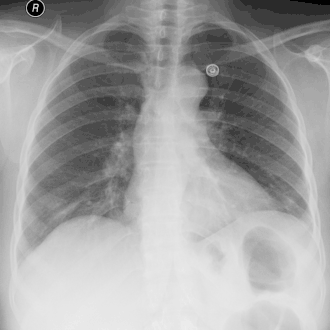

O diagnóstico é sugerido pela anamnese e exame físico, e complementado pela radiologia, exames laboratoriais e toracocentese.

A radiologia é uma ferramenta essencial, e deve ser realizada nas incidências póstero-anterior e perfil. A radiologia permite ainda avaliar de modo grosseiro o tempo de evolução do empiema.